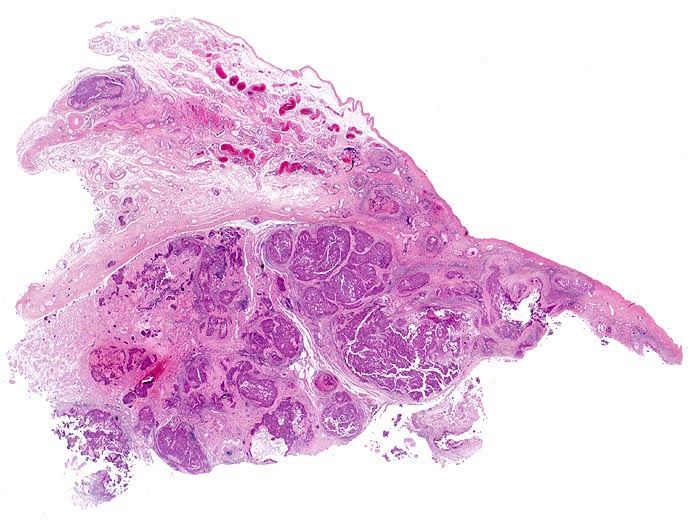

Makroskopisch bilden die embryonalen Karzinome unscharf begrenzte, weiche, graubraune Tumorknoten mit Einblutungen und Nekrosen.

• Kein residuelles nicht neoplastisches Hodengewebe.

• Tumorinfiltration des peritestikulären Fettgewebes.